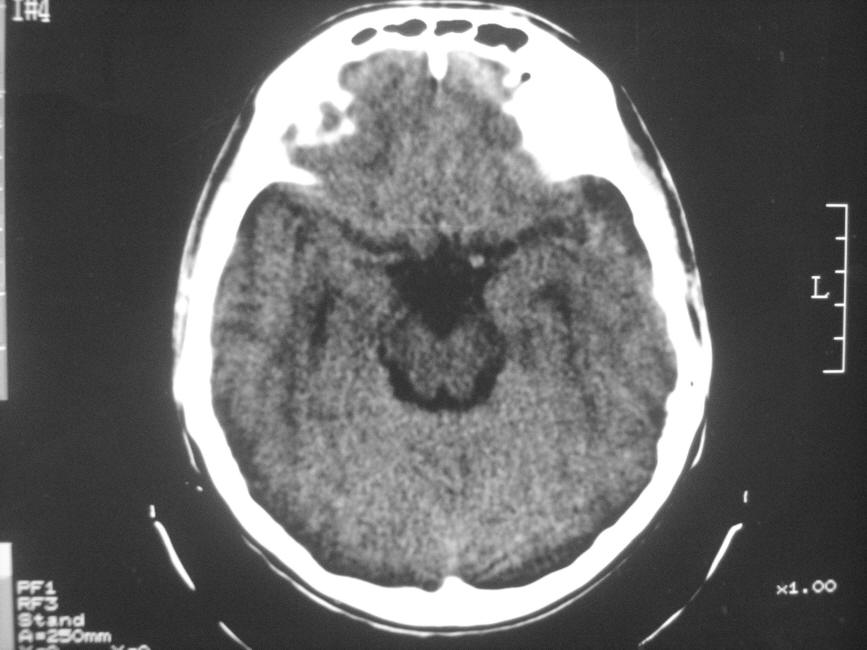

以下是引用zzyy在2008-6-16 10:13:00的发言:[br]两侧脑白质呈对称性密度减低,病儿有发热及脑膜刺激征。考虑急性病毒性脑炎。